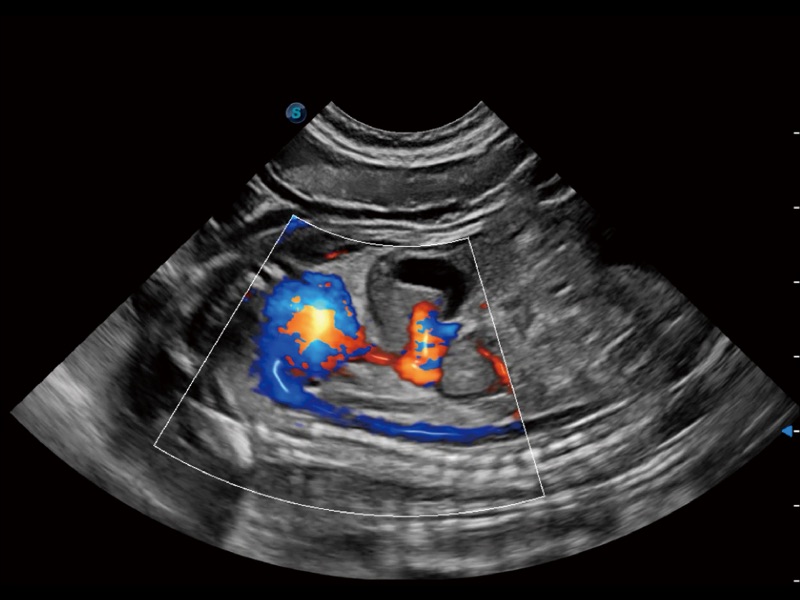

大型犬、马科、农场动物及大型异宠动物

通过创新的 Matrix E自适应滤波器和超长时间域算法,极大提升超低速微细血流的检出能力,同时更精准地滤除软组织和噪声信号,为兽用医生提供以往无法通过常规血流获得的疾病诊断信息。

通过色彩血流和实时宽景相结合,可观察到完整的静脉或动脉的血流,方便医生检查。实时扫查过程中,如有任何操作失误也可以很容易地进行回扫擦除,而不会中断扫查。